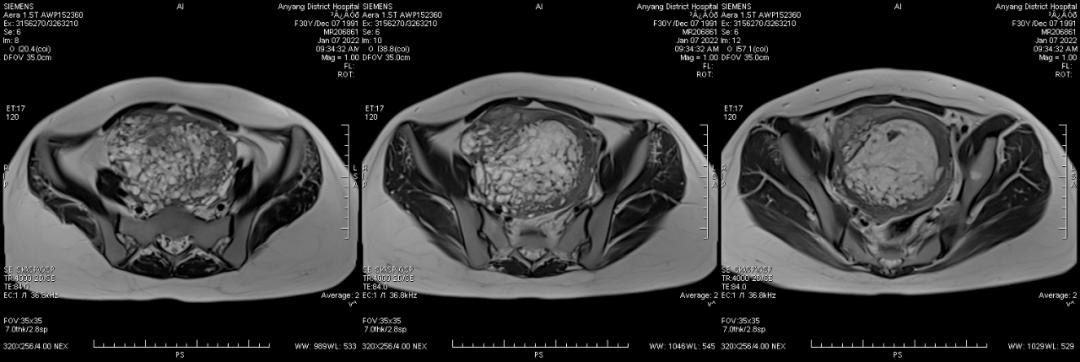

病例二

女,30 岁,侵蚀性葡萄胎,穿透宫壁全层。引道出血 20 多天,既往有 3 次人工流产病史。